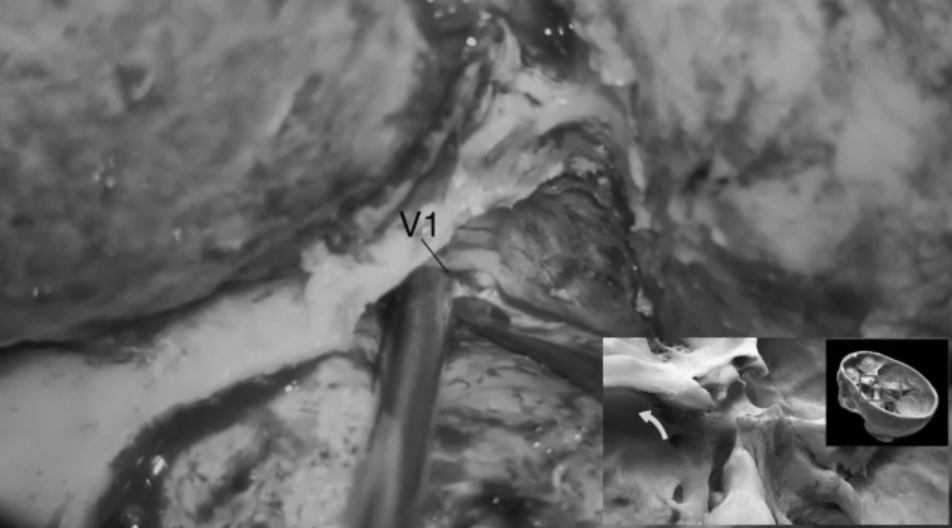

定位三叉神经V1段,以助显露眶上裂;游离并进一步解剖眶上裂,识别、电凝并切断眶脑膜韧带。

识别并磨除前床突;磨除时仔细分辨气化部分,电凝蝶窦黏膜,避免穿破。

进一步向内磨除视神经管及视柱,完成前床突切除术,此后进入硬膜内操作:弧形剪开硬膜,立即可见位于额颞叶之间的肿瘤。